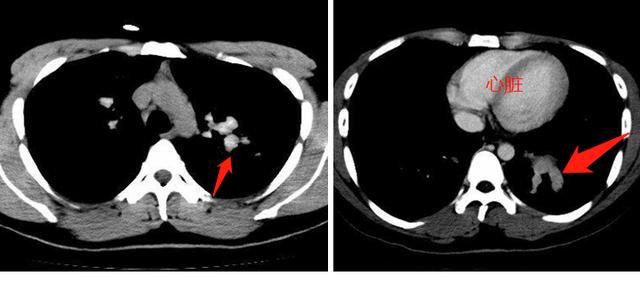

我们再接着看纵隔窗,就能明白这是什么疾病了:

从这两张纵隔窗CT片上,我们发现支气管内的充填物密度很高,偏灰白色,比胸壁肌肉密度高很多。

这种高密度的粘液栓对诊断有很高的提示意义,说明这里面存在曲霉菌感染(一种常见真菌),这种真菌能富集空气中的铁、锰离子,造成密度增加,提示诊断。这种粘液嵌塞伴高密度,文献报道约50%的病人可以在CT片上见到。